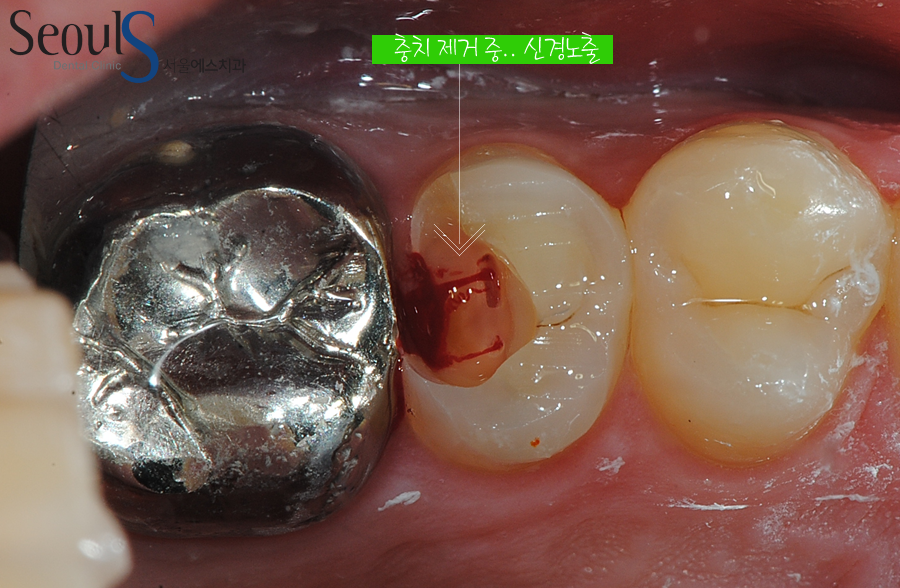

충치 때문에 치아가 깨진 모습입니다

심한 통증과 검게 충치가 진행되고 있습니다

통증으로 봤을 때 충치가 신경까지 진행 되었다고 예측할 수 있는 상황입니다

진행되고 있는 충치를 제거하고 있습니다

충치 제거 중 피가나고 있습니다

이는 신경조직이 외부로 노출 된것을 의미하며

신경조직이 세균에 감염이 된 상태입니다